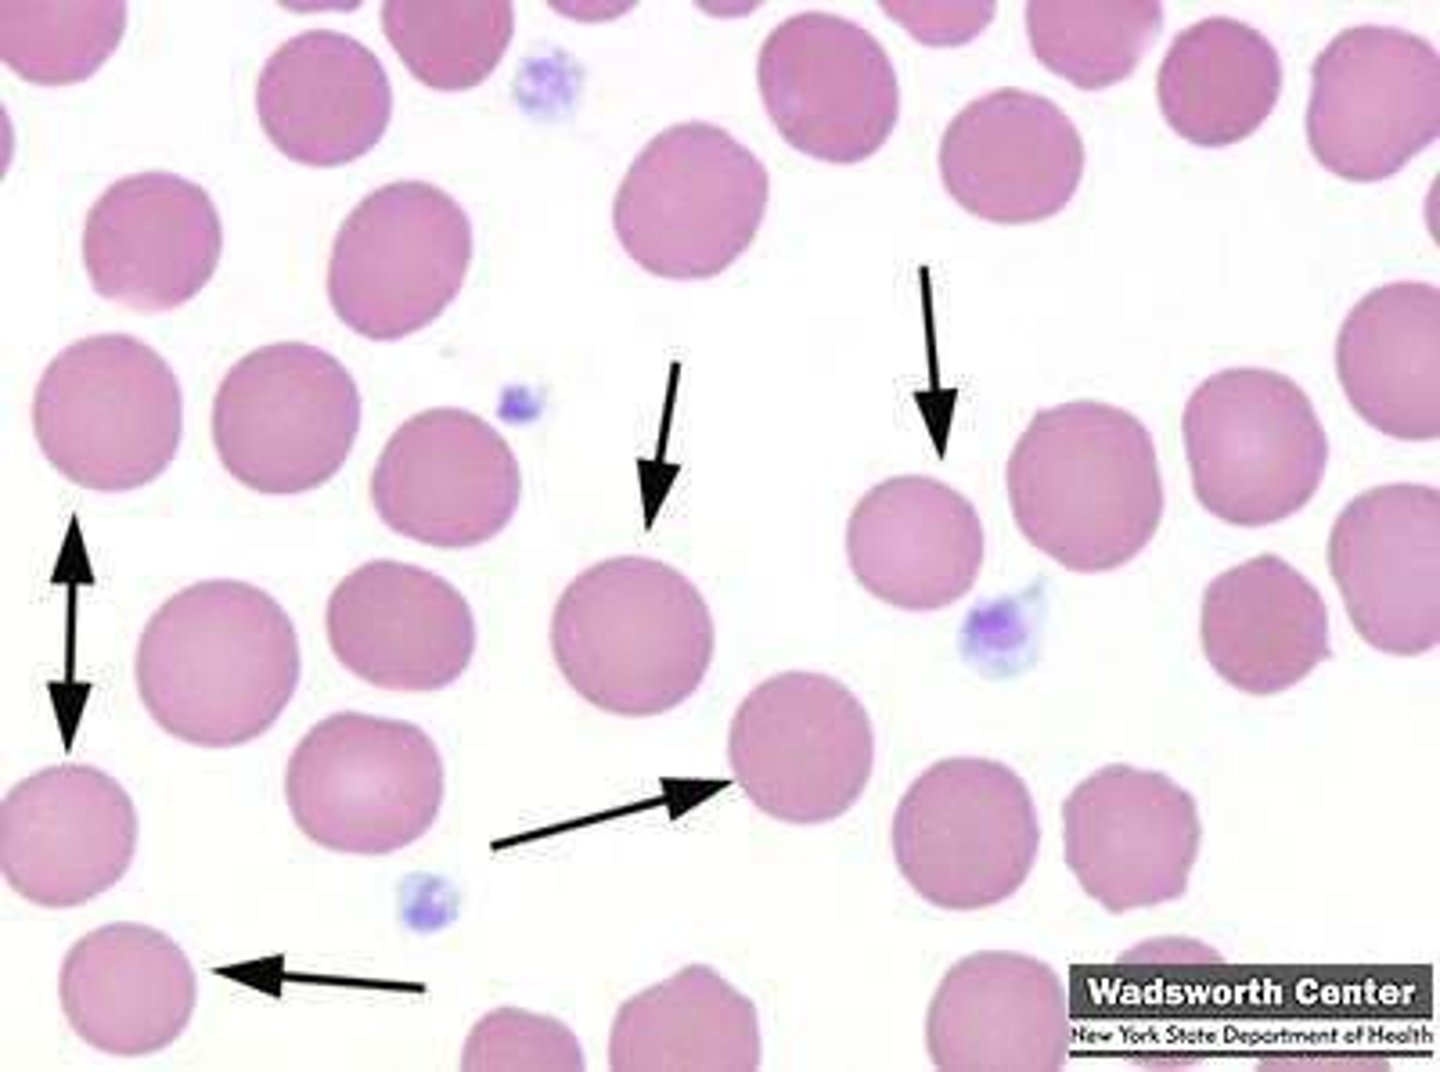

anisocytosis

MAMMAL

mixture of mature and immature RBCs

- variation in RBC size